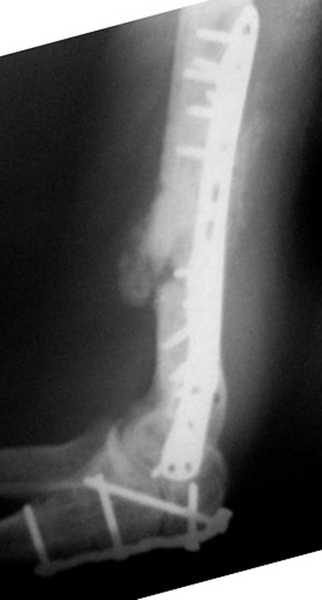

На примере два случая, извиняюсь за качество снимков, снимки и случаи из

Первая больная с "успехом" была прооперирована 6 раз различными методами

открытого и закрытого остеосинтеза, включая то, что в Кисловодске

заезжим австралийским "кудесником" на ложный сустав уложена скорлупа от

страусиновых яиц. Последняя операция одиноким локинг плейт в одной из

клиник.

Через год по поводу тех же проблем сделали ревизию, оригинальную

пластину оставили как есть, только укрепили добавлением еще одной

пластины и сделали костную пластику.

Через два месяца увидели признаки консолидации.

Вложение не в текстовом формате было извлечено…

Имя     : 1 AP humerus.jpg

Тип     : image/jpeg

Размер  : 19421 байтов

Описание: отсутствует

Url     : http://weborto.net:8080/pipermail/ortho/attachments/20080223/b621f987/attachment-0008.jpg